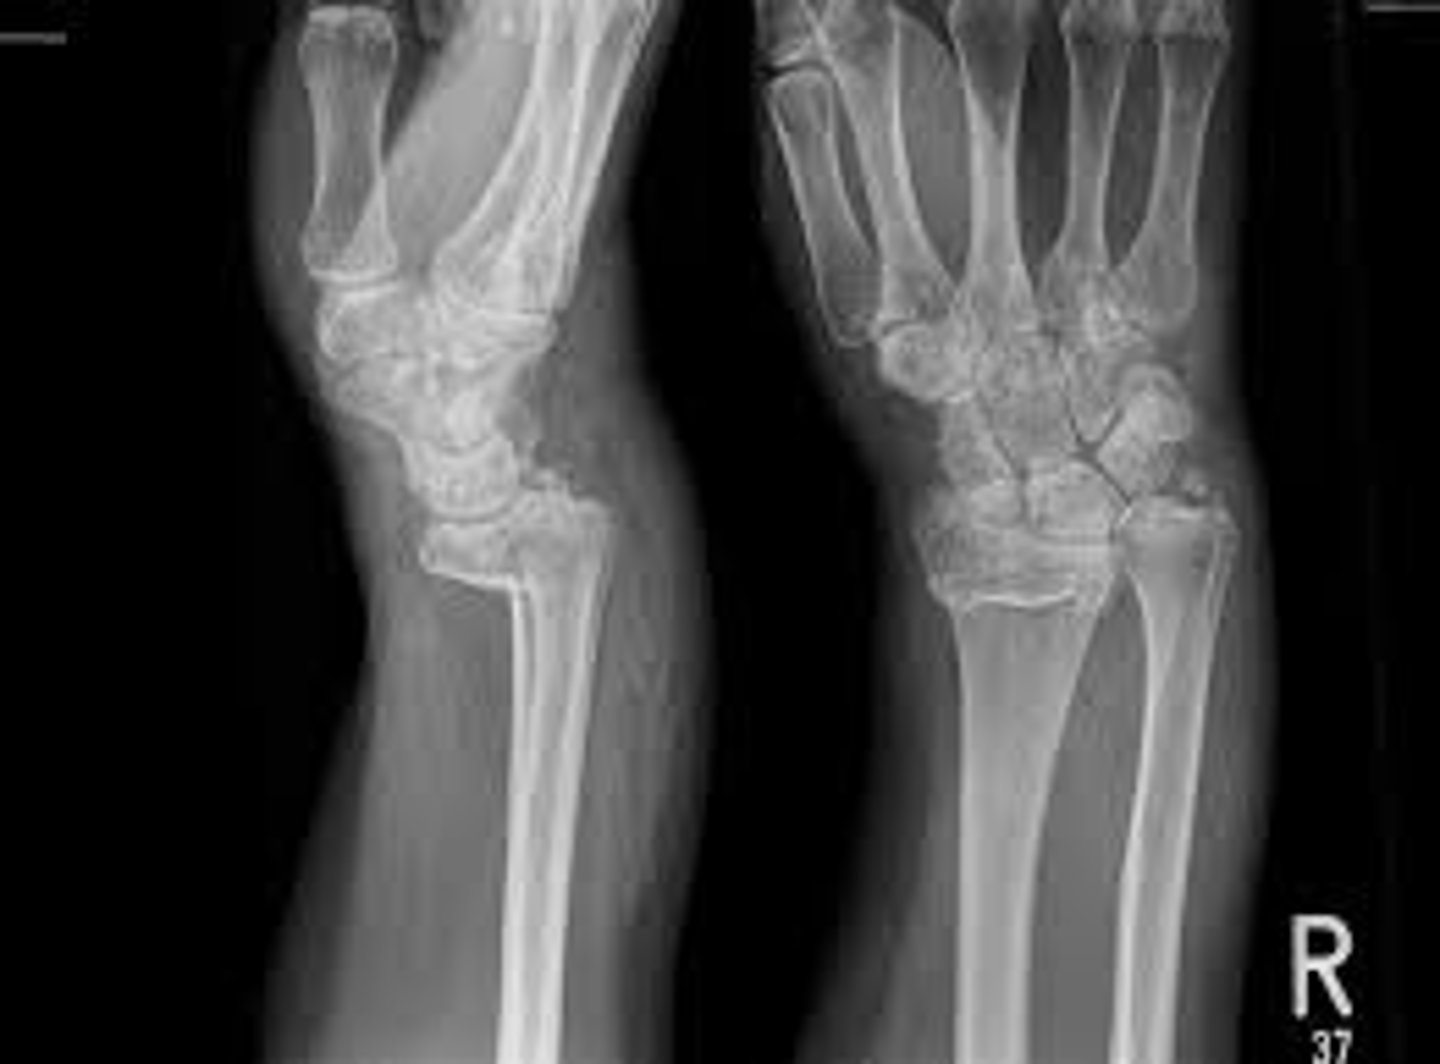

Fracture of distal radius with posterior displacement

Colles' fx